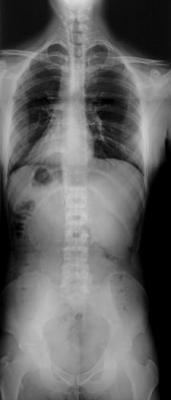

iCRco will debut “the ONLY 52” DR in the world”, says Stephen Neushul, President and CEO of iCRco. This machine has Scan Head Technology that provides one continuous image and eliminates stitching. Its ultra-high resolution, full body scanning is capable of scanning a complete spine.”

Other features found on the new “Longbone” DR machine are a solid state sealed sensor and the fastest speed you will find for anything that long.